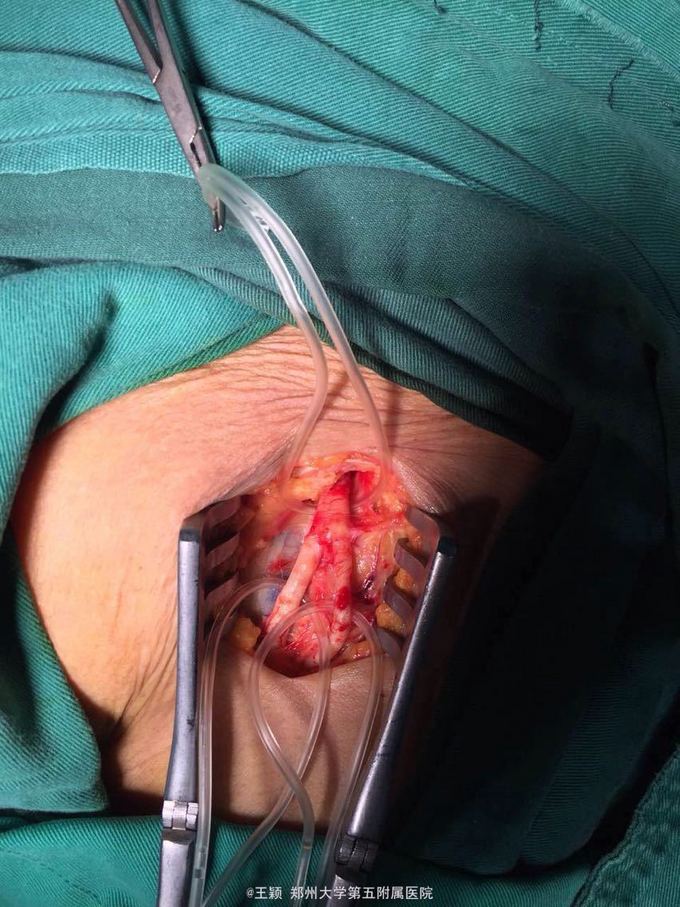

腹主动脉骑跨栓,心律不齐 房颤 急诊全麻下行双股动脉切开去栓及造影术,术后抗凝,解痉,改善循环,营养神经,抗炎,利尿及碱化尿液,监测肾功能,电解质等,随时准备透析治疗